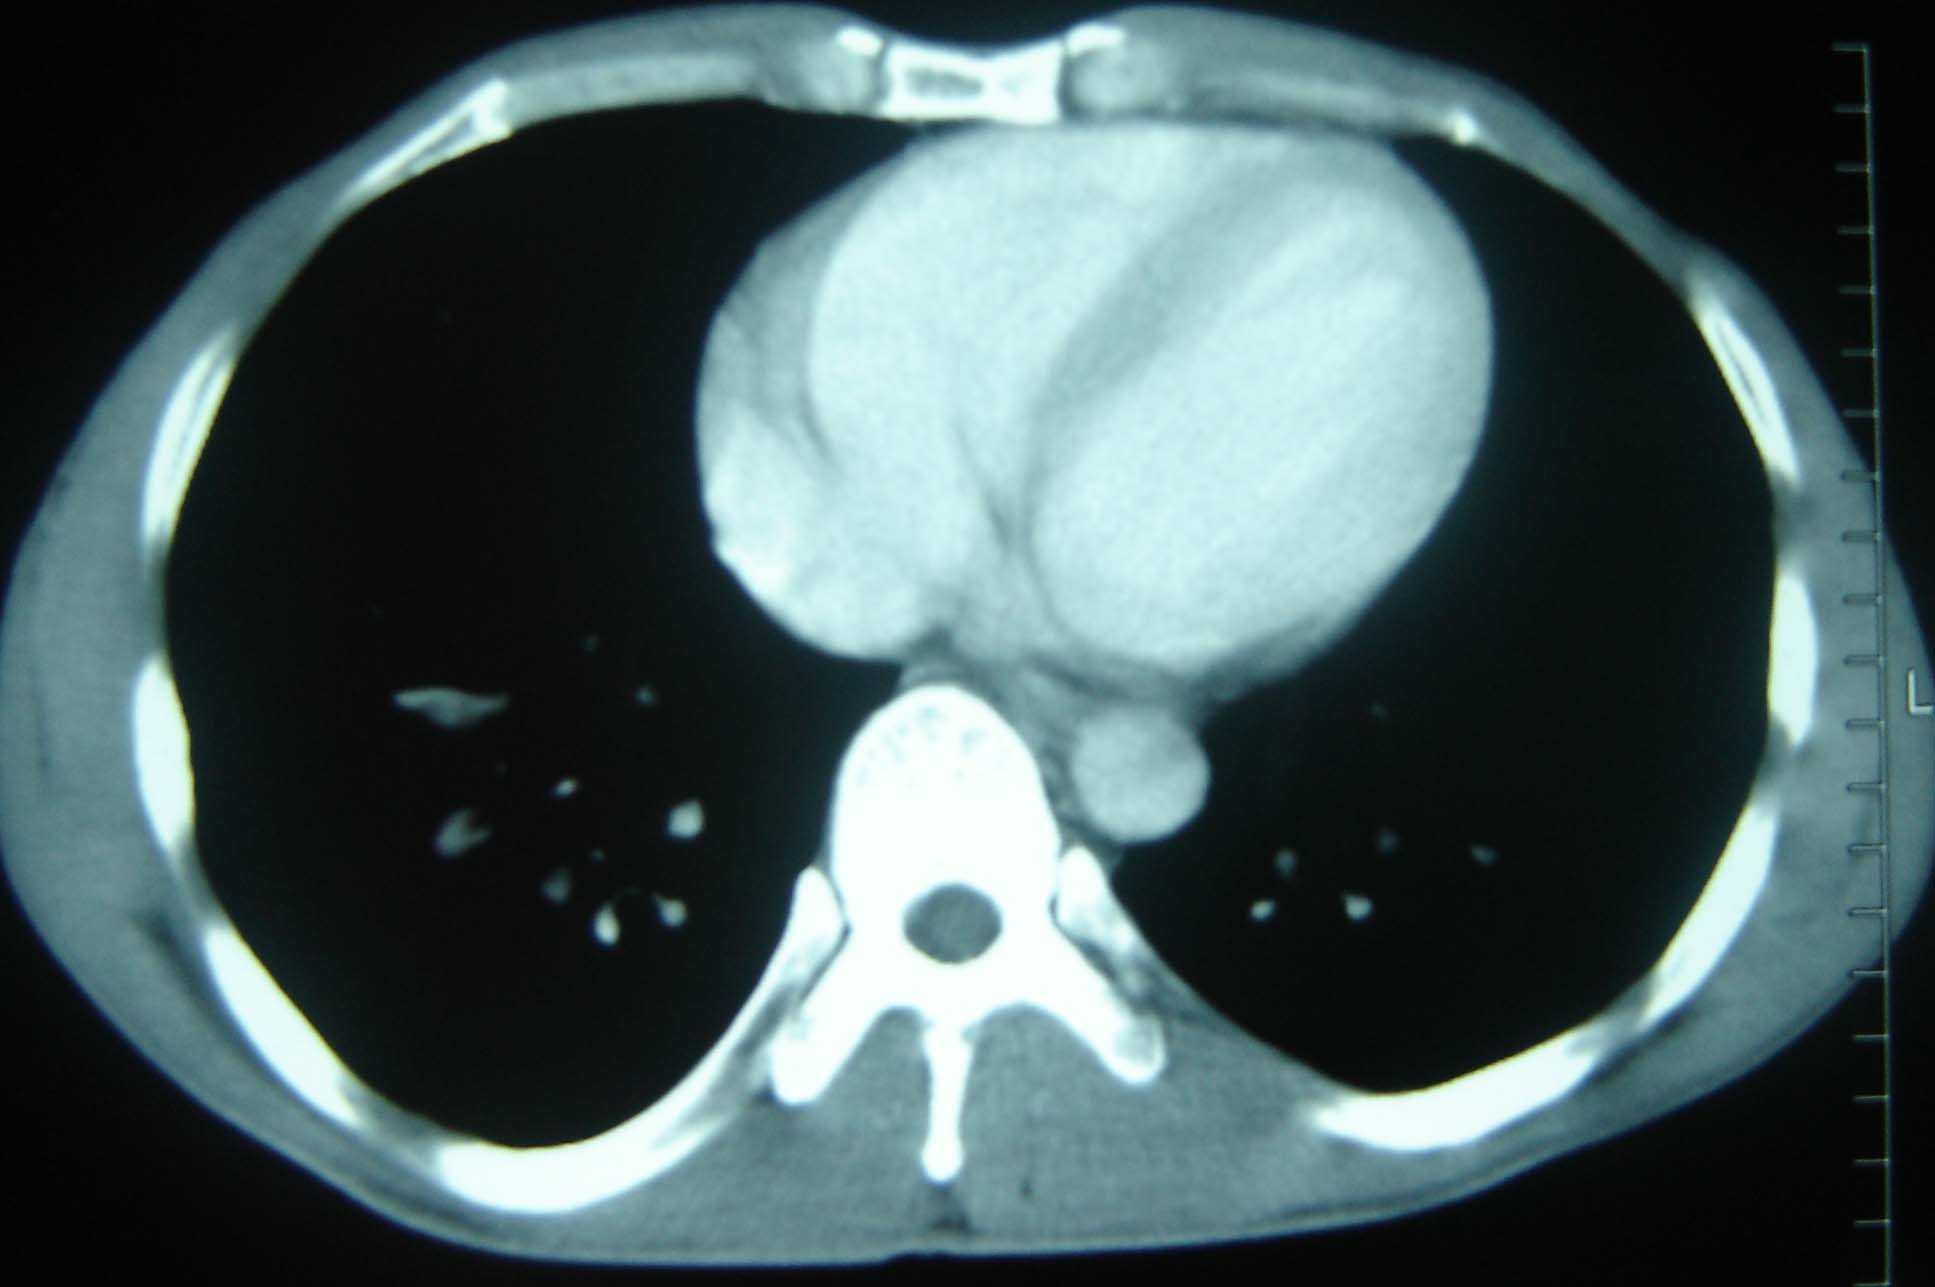

标题: CT25321:两肺多发结节 请会诊 [打印本页]

男 、43岁,咳嗽胸痛,装修工,平时接触粉尘较多,有吸烟史10多年,纤维支气管镜检查未发现异常,胃镜、腹部b超检查亦未发现异常,颈部淋巴结活检未发现肿瘤细胞。